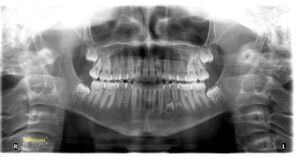

أسنان بشرية تحت صورة بانورامية للأسنان.